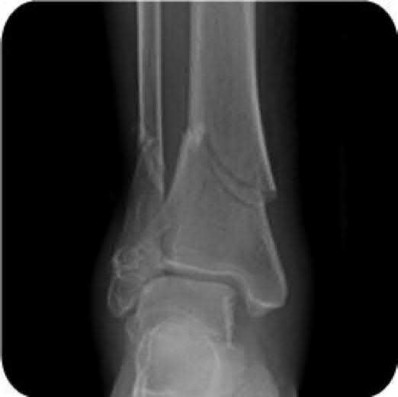

Figures A to C show radiographs of a 70 year-old male who fell on the ice 5 days ago. He could initially walk after the fall, but he is now unable to weight-bear on the leg due to pain. Physical examination shows diffuse ankle swelling, with no medial sided ankle tenderness. He is neurovascularly intact. The patient does not smoke and has no medical history. A gravity stress radiograph is demonstrated in Figure

D. After closed reduction, there is 2 mm of fracture displacement, no talar shift and the talocrural angle = 83 degrees. What is the most appropriate treatment?

The patient has a 5 day old Weber B fibula fracture with a well reduced mortise and stress radiograph that demonstrates no instability of the mortise. The appropriate treatment would be a period of immobilization followed by advanced weight-bearing as tolerated.

The patient has an isolated lateral malleolus fracture. These fracture are stable if the deltoid ligament is intact, and unstable if the deltoid ligament is disrupted. The competency of the deltoid ligament can be evaluated with a stress radiograph which is completed by placing the ankle in maximum dorsiflexion and 15° of internal rotation while an external rotation force is applied to the foot. A stress radiograph (manual or gravity assisted) is positive if there is subluxation of the talus during the exam. The presence of tenderness or swelling medially at the ankle has been shown to be a poor indicator of medial-sided injury. The clinical utility of MRI scans in ankle fractures is controversial.

Figure A demonstrates an AP radiograph of a Weber B fibula fracture with minimal medial clear space widening.

Figure B demonstrates a mortise radiograph of a Weber B fibula fracture with a congruent mortise.

Figure C demonstrates a lateral radiograph of a Weber B fibula fracture with a congruent mortise.

Figure D demonstrates a stress radiograph with minimal medial clear space widening.